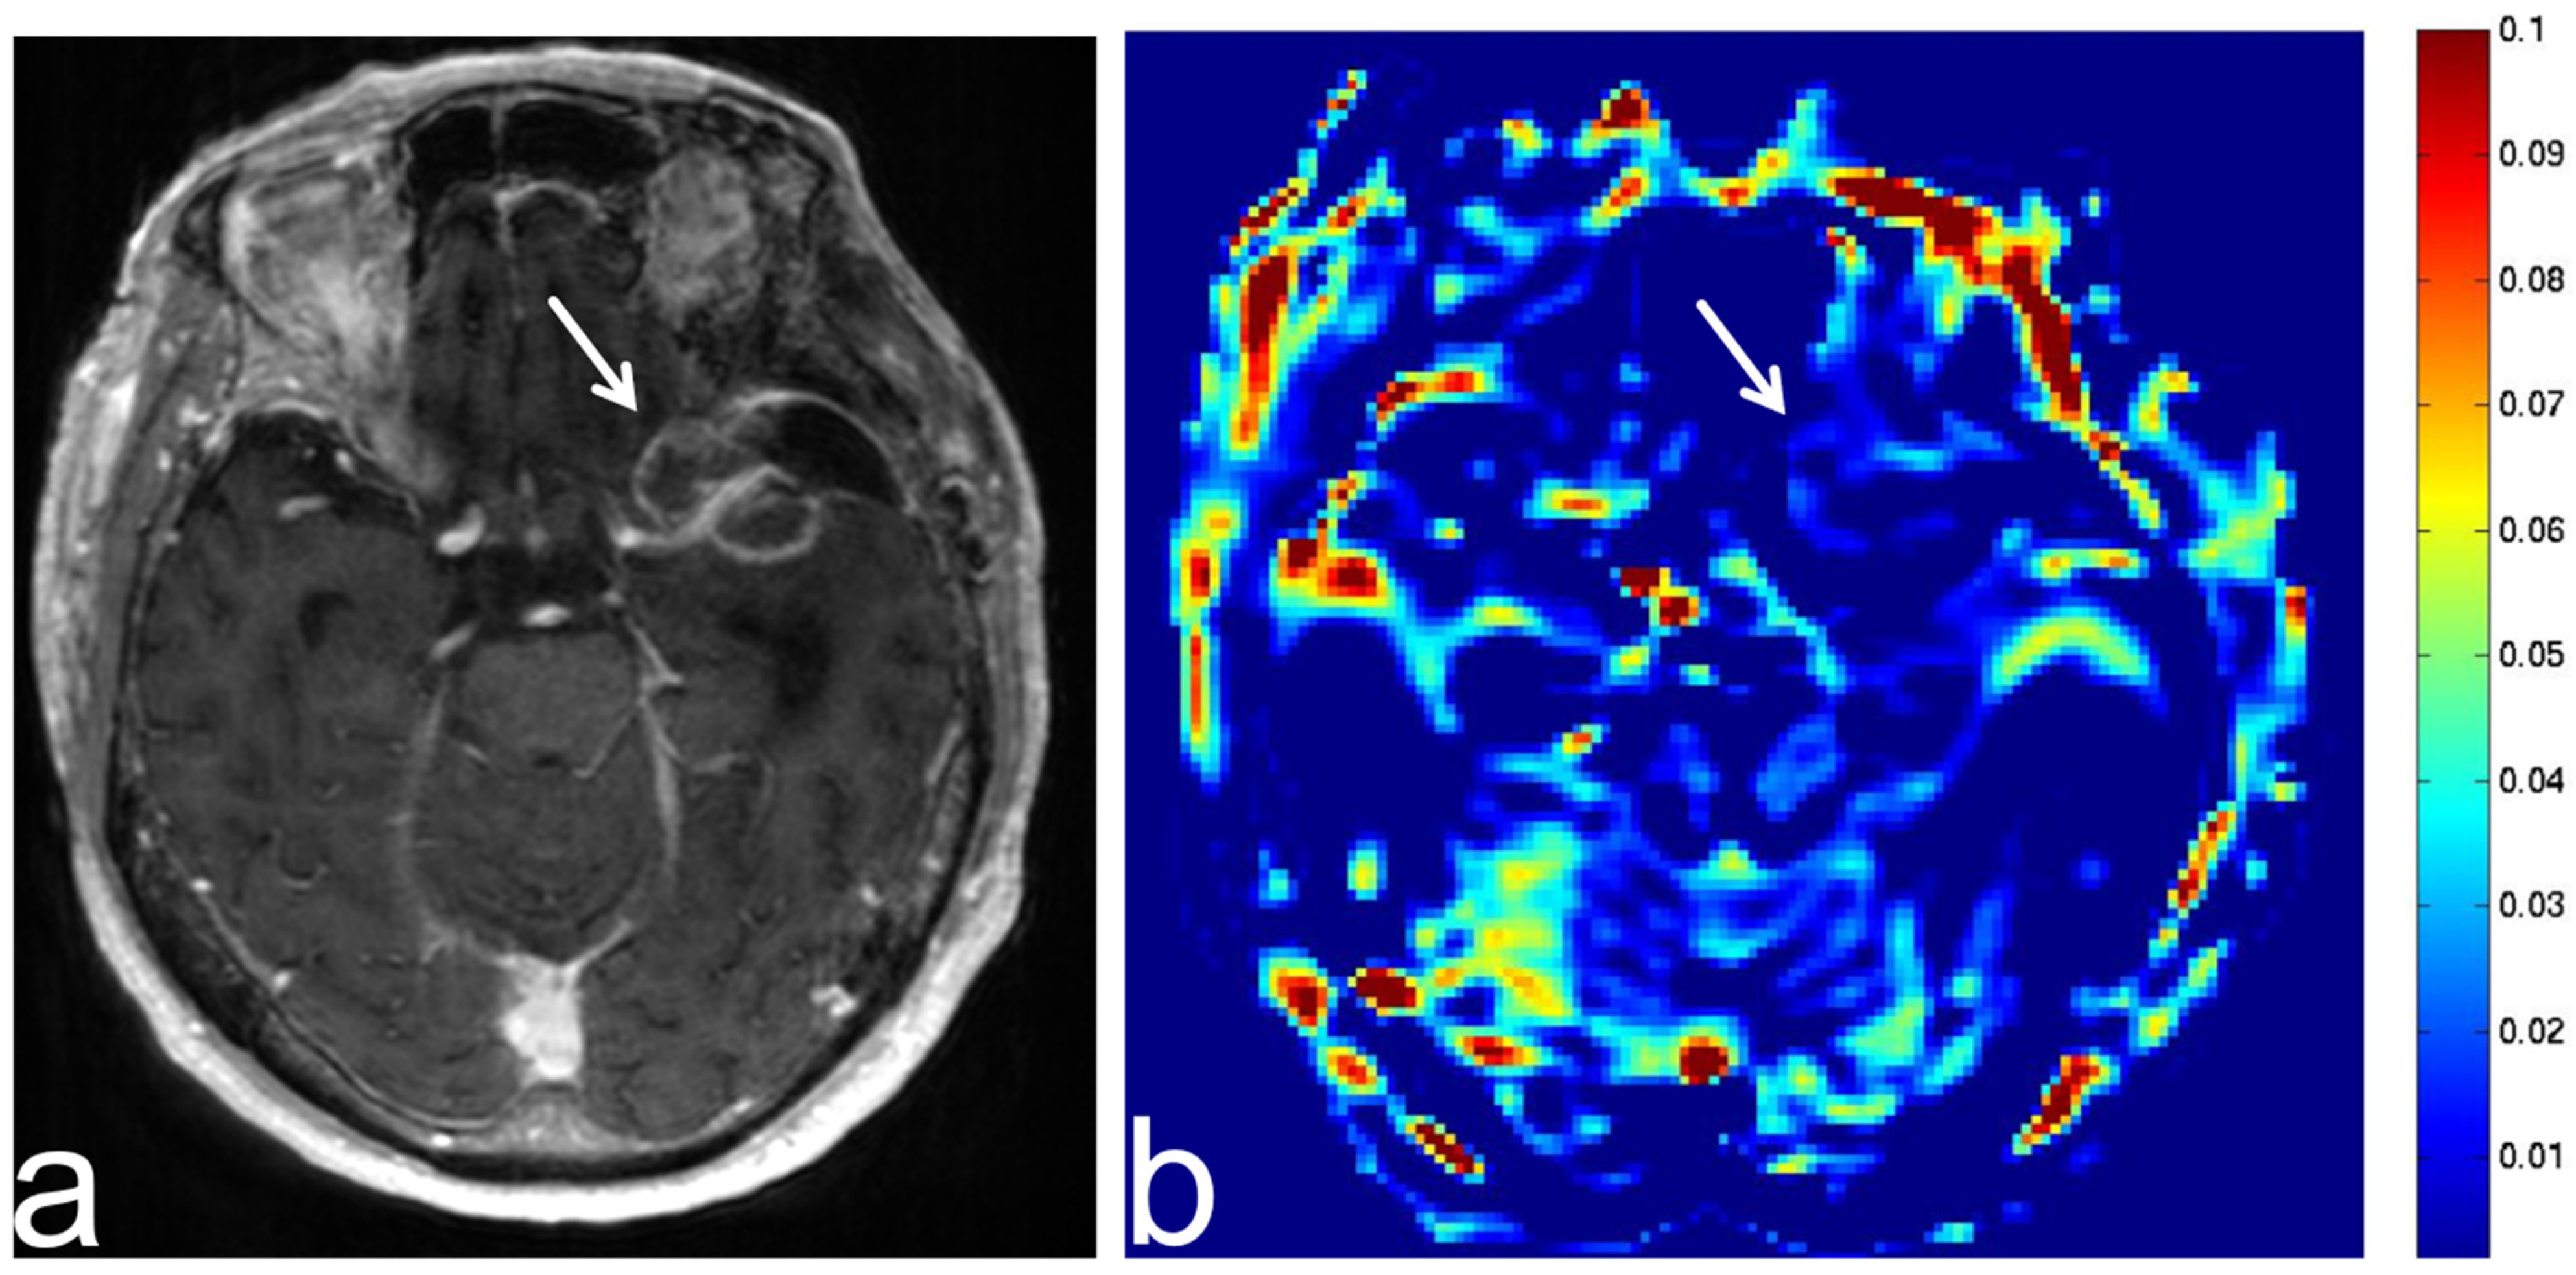

5.4. Malignant Lymphoma

5.5. Brain Metastasis